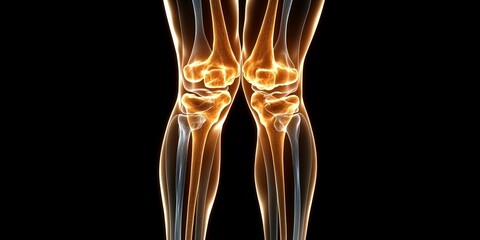

Podobny obraz Medical Elbow Anterior View X-Ray Radiograph Illustrating...